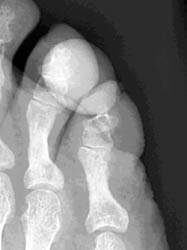

55 years old male with slowly growing mass at the tip of the plantar aspect of 4th toe. Plain films demonstrate well defined non-calcified mass at the tip of plantar aspect of 4th toe. MR imaging demonstrates this mass has low to intermediate signal intensity on all the sequences.